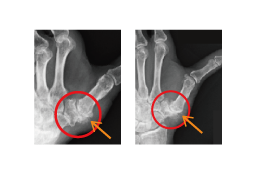

母指(親指)の根元にある母指CM関節の軟骨が摩耗するなど、亜脱臼状態(ズレたり、外れかかること)になると、「物をつかむ」「瓶のふたを開ける」「包丁で何かを切る」といった作業で母指に力のかかる動作で痛みを伴うようになります。これが母指CM関節症です。

40歳以上、特に閉経後の女性や、つまみ動作の多い職業の方が発症しやすいのが特徴です。また男性は、力仕事やけがによって発症するケースがよくみられます。

※赤丸内:関節軟骨は消失し、大きな骨棘が形成されています。

まずは装具装着などによる保存的な治療を行いますが、疼痛が改善しない場合は手術となります。 手術方法もさまざまですが、当院では、ミニタイトロープを用いた母指CM関節形成術や、自分の腱を用いた関節形成術を行っております。